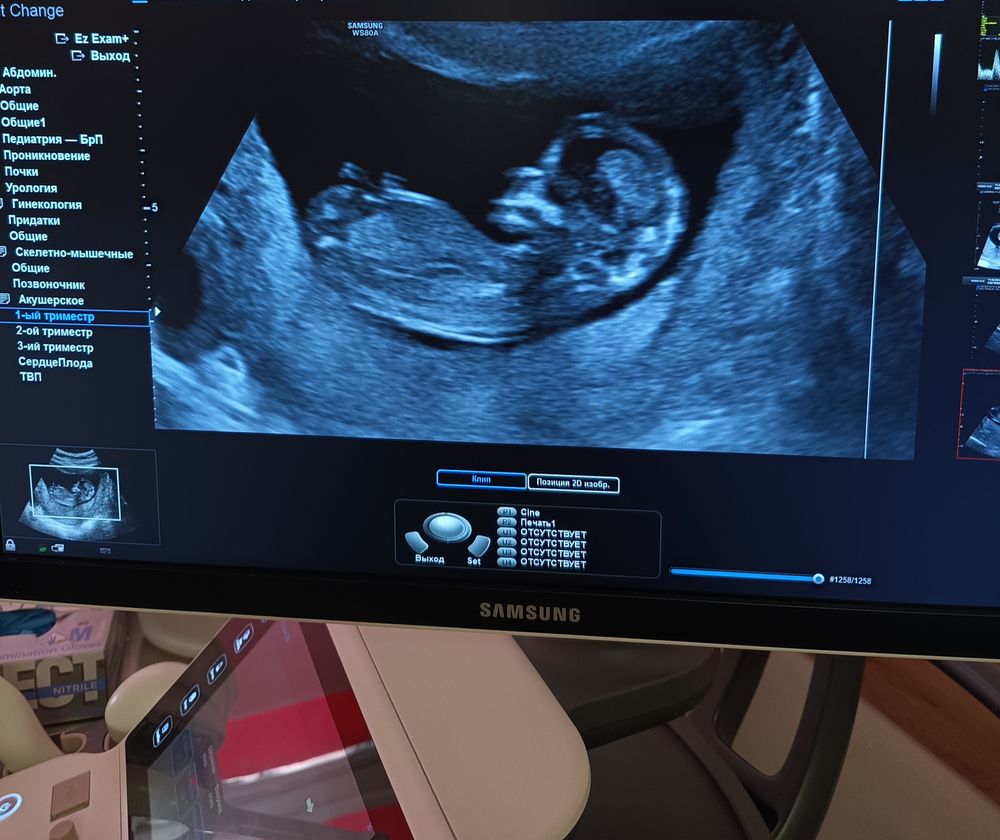

Последнее фото - скрининг в 12+4

Последнее фото - скрининг в 12+4